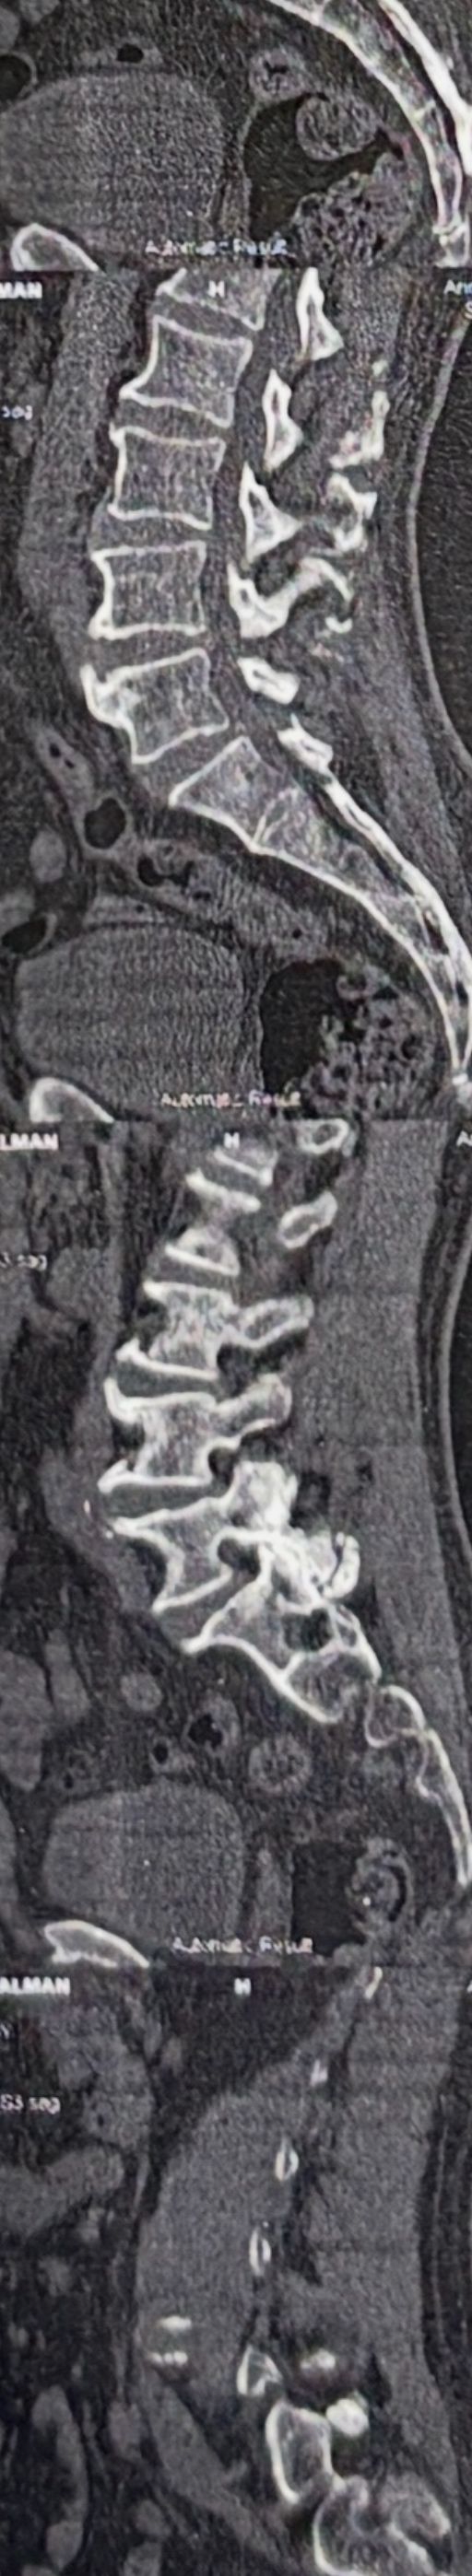

Few weeks ago I posted a case with an old TB spondylitis and listhesis with old fractures and severe canal stenosis (in her lower lumbar). A neurosurgeon who works with us at my clinic saw her in the second session

I attached her CT scan. Her PPD which was positive 2 months ago now it’s less than 3 mm. Since this patient has just low back pain and no radicular pain and can walk easily our neurosurgeon suggested no surgery and we emphasized that she has to complete her medication and be under her infectious diseases specialist

And if other signs and symptoms develops have to see surgeon again

42 years old female presented to my clinic yesterday on May15/2025 with chronic Low back for 2 yrs. She is from afghanestan and arrived to tehran 3 month ago. Visited pain specialist 3 months ago who just did PPD test and gave her Anti TB medication. In examination just had severe focal khyphosis from L3 to L5 without any tenderness. Her mri was done 2 months ago. Report is in Farsi and mentions of paraspinal puss/ fluid collection esp in psoas muscles, with extension of fluid collection to R pelvic region. Had 2 site of severe canal stenosis due to previous fractures of L3,4,5 and movement of fractured bones to the canal with complete distractions of those levels discs with fusion of L3 to L5

I ordered C T scan of lumbar and pelvic MRI / chest x r and reffered her to neurosurgon and infectious disease specialist to get full assessment and possible hospitalized for biopsy and surgery

As you know doctors of chiropractic would never. give treatment to patients with spinal Discitis/ osteomyelitis/ metastasis/ fracture( absolute chiropractic contraindications for treatment)